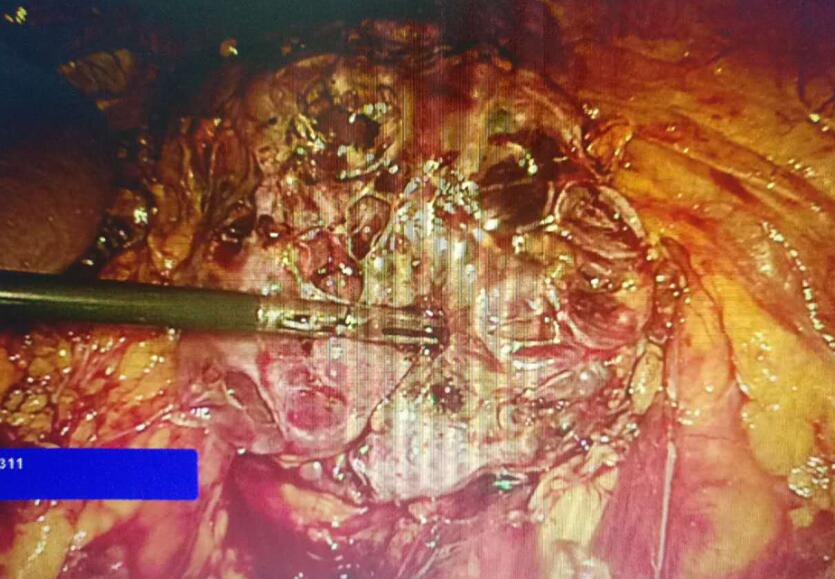

图二:术中多囊肾表现

手术采用经腹腔途径气管插管,患者于全身麻醉下右侧卧位。手术医师在患者左肋缘下与胸骨旁线交叉处下方二横指(A点)建立气腹后,于平脐左锁骨中线(B点)采用10 mm Trocar穿刺成功,直视下在A点、肋缘下腋前线处(C点)采用5mmTrocar穿刺后,沿左侧结肠旁沟纵行切开后腹膜,上至膈肌,下至肾脏下缘,再将肾周筋膜完全打开,保护好肾门血管、淋巴管及输尿管,彻底游离左侧肾脏,显露肾脏囊肿(见图二)。